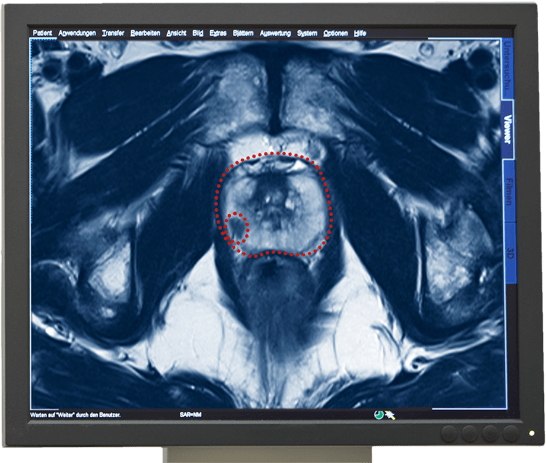

Vroegtijdige en zekere diagnose door multiparametrisch MRI-onderzoek van de Prostaat

Het multiparmetrisch MRI-onderzoek van de Prostaat geldt als het zekerste beeldmateriaal om prostaatkanker te diagnosticeren. Met dit onderzoek kan een kankergezwel gevonden worden en de eigenschappen daarvan vastgesteld en beoordeeld worden.

De informatie over de kwaadaardigheid van een tumor wordt geleverd door een weefselanalyse. Daarvoor worden weefselbiopten uit het verdachte kankergezwel genomen. Met onze Prostaatbiopsie kunnen wij door MRI-sturing gerichte biopten uit het gezwel nemen, pathologisch onderzoeken en de Gleason-score bepalen.

MRI-onderzoek als basis voor adequate therapie bij Prostaatkanker

Een multiparametrisch MRI-onderzoek van de prostaat kan de volgende informatie geven, die voor de aansluitende therapie behulpzaam kan zijn.

- Diagnose van de kwaadaardige tumor

- Plaats van de tumor

- Bepaling van de grote en volume van een tumor

- Expansie van de tumor

- Eventuele aantasting van de omliggende structuren of organen

- Eventuele aantasting van de lymfeknopen in het bekken

- Eventuele aanwezigheid van uitzaaiingen in de bekkenbeenderen